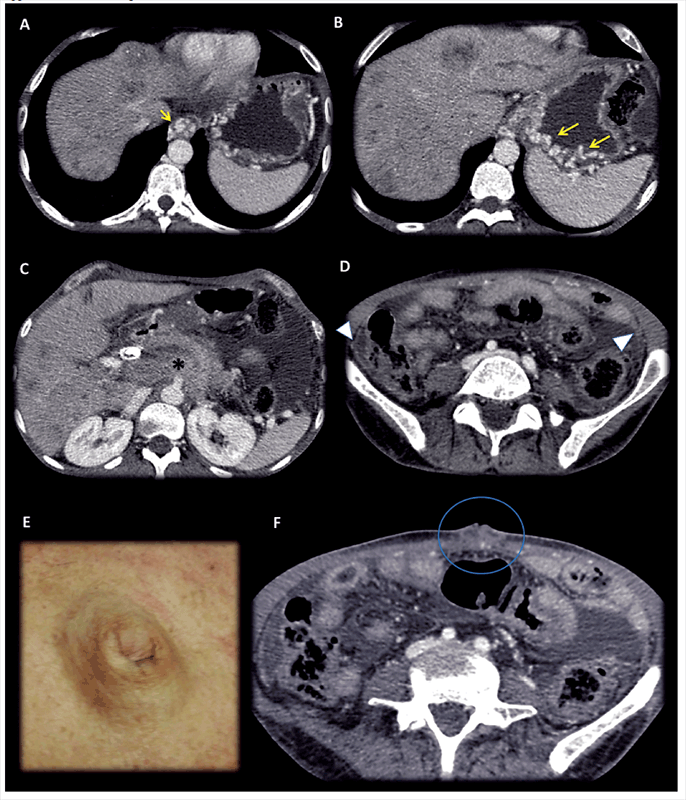

Contrast enhanced MDCT axial slices, in portal-venous phase: Images shows hipovascular liver metastasis and an extensive infiltrative retroperitoneal (*), vascular and peritoneal involvement. A SMJN can be appreciated in the umbilical area (E and F). Clinicians thought that they were leading with a non-complicated umbilical hernia. Left-sided portal hypertension syndrome consists in gastric and esophagus varices with patent portal vein and extensive splenic vein thrombosis secondary tumoral invasion and replacement of splenic vein (arrows). The peritoneal involvement denotes a small amount of loculated ascites and a slightly thickening of the peritoneum with some small nodular areas (arrow head). In this exceptional case, the omentum does not appear to have macroscopic involvement.

Contrast enhanced MDCT axial slices, in portal-venous phase: (A, B, C) Huge Gastric neoplastic mass with transmural involvement with non-defined borders that invades the omentum [white asterisk (*)], hepatoduodenal and gastrohepatic ligaments [black asterisk (*)]; hipovascular liver metastasis (yellow arrows). (D, E) Metastatic umbilical nodule SMJN (volume renderings, images, blue arrow and circle).